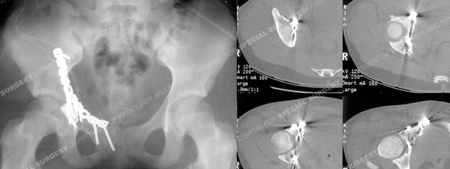

Fracture surgery was performed using an ilioinguinal approach. The fracture was reduced and stabilized using a contoured 10-hole pelvic reconstruction plate and screws and placement of a spring plate along the anterior wall fracture. Postoperative CT scan images (right images) illustrate an adequate reduction.

The patient returned at 8.5 years following surgery and radiographs demonstrate a healed acetabular fracture and maintenance of joint space. She had fully returned to full activities and reported no pain.